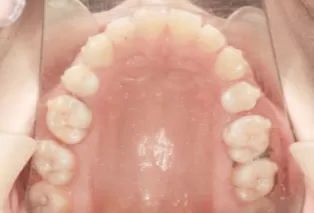

Intraoral photos